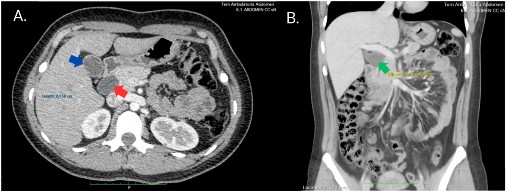

Asimismo, se realizó un estudio tomográfico inicial en el que se observó una imagen hipodensa proyectada a nivel del colédoco extrapancreático, que se reportó como posible ectasia de dicho colédoco, con menor probabilidad de ser un componente quístico. No se definieron lesiones focales mediante este método (Figura 2).

TEM: tomografía espiral multicorte

Figura 2 A. Corte transversal en TEM abdominal donde se evidencia la dilatación de la vía biliar extrahepática de aproximadamente 2,75 cm de diámetro (flecha roja), en las mismas dimensiones que la vesícula biliar (flecha azul). B. Corte coronal de TEM abdominal donde se evidencia la dilatación de la vía biliar extrahepática (flecha verde).